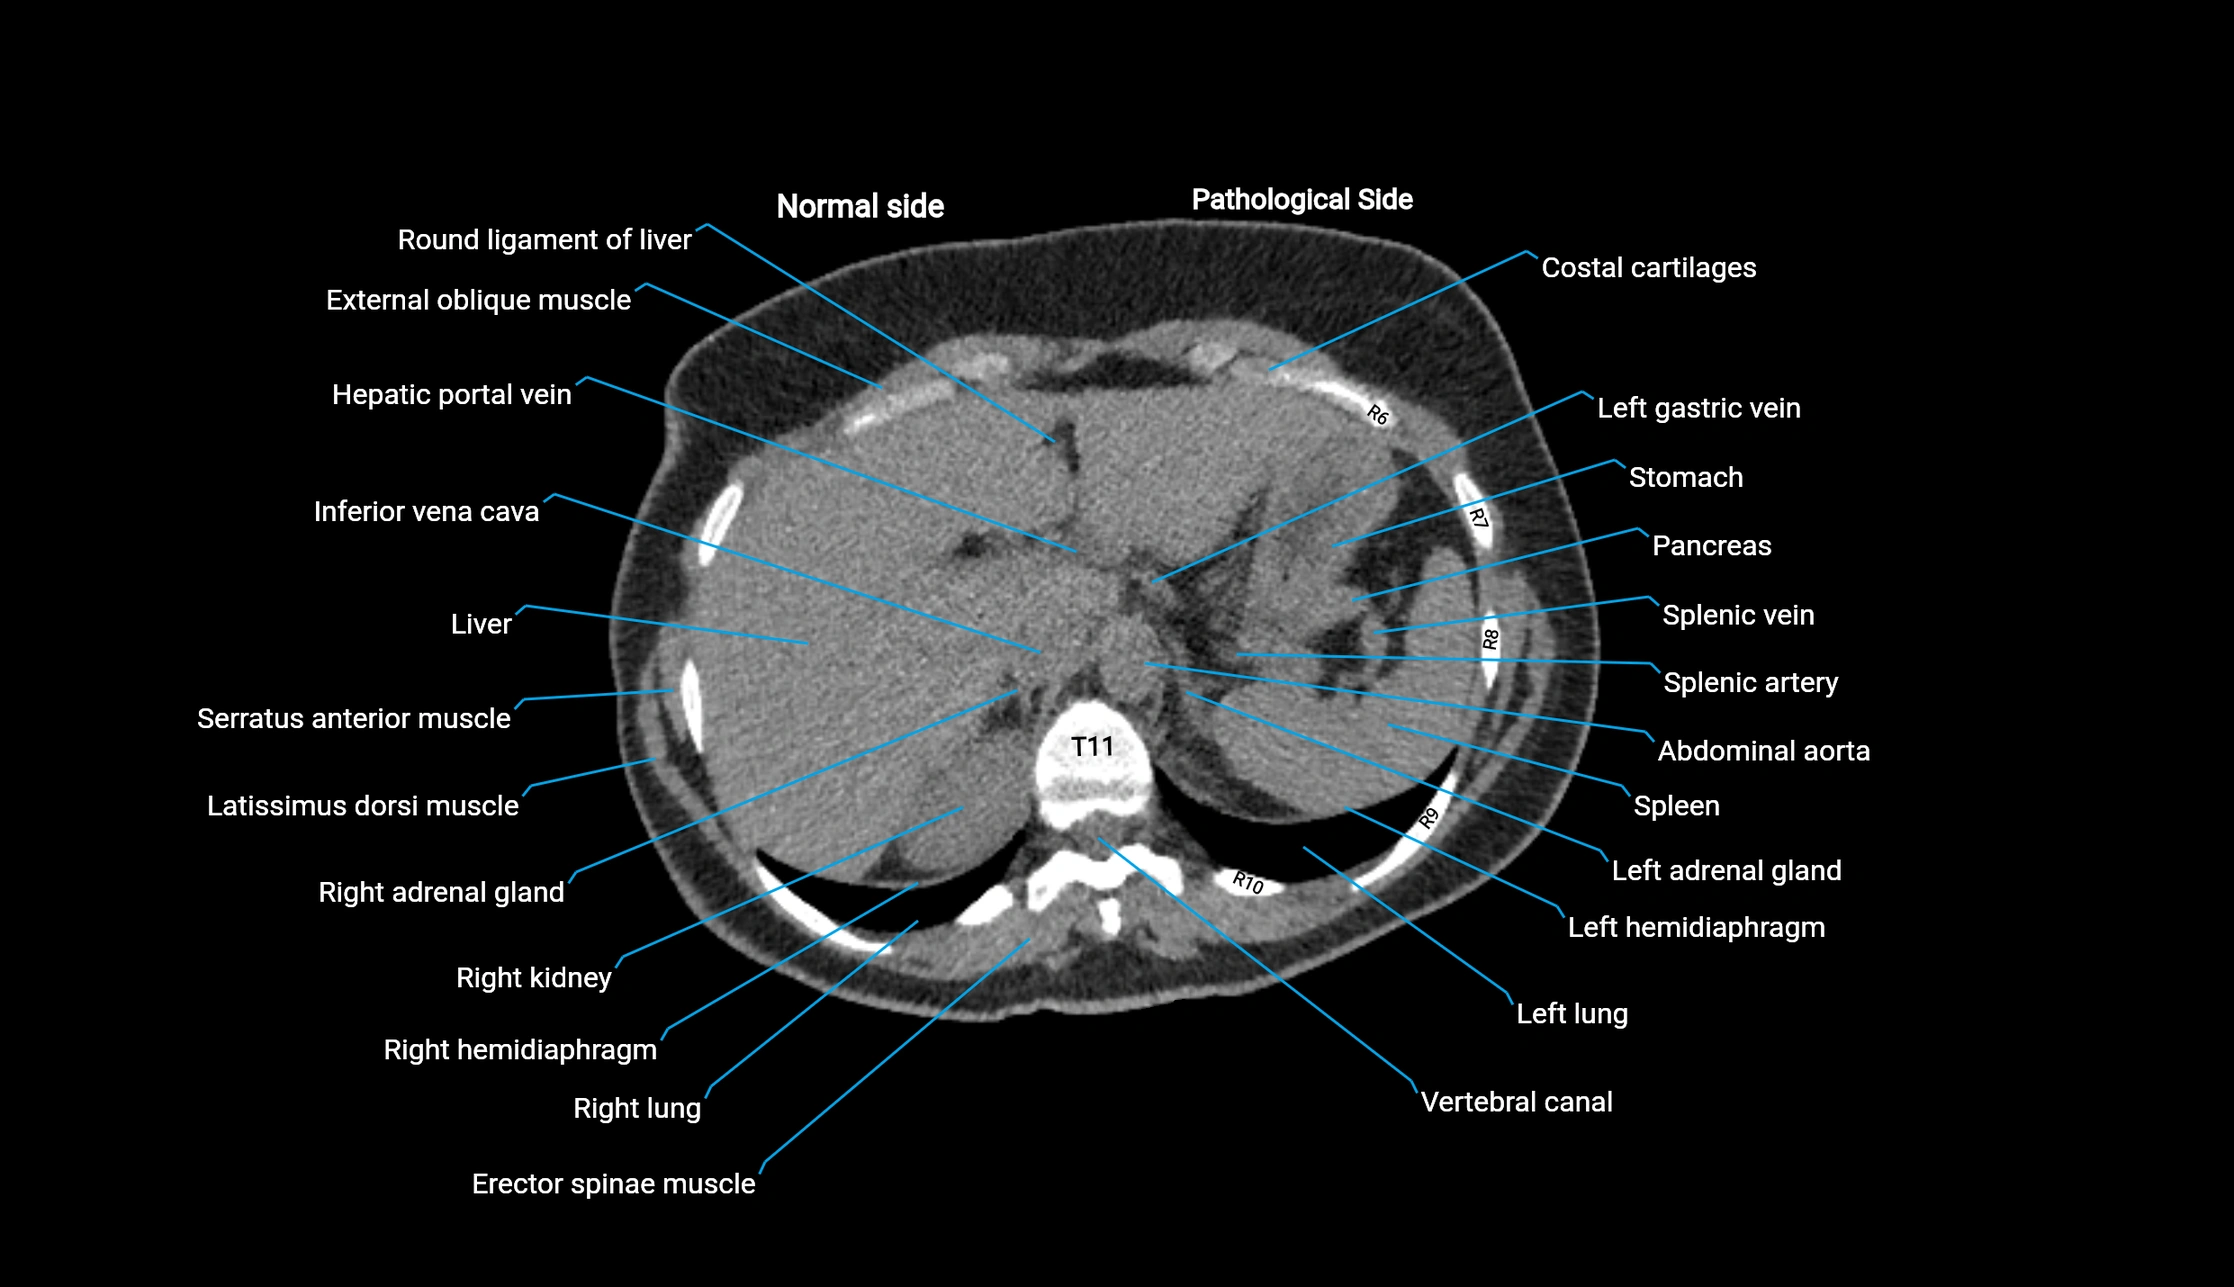

CT image

image